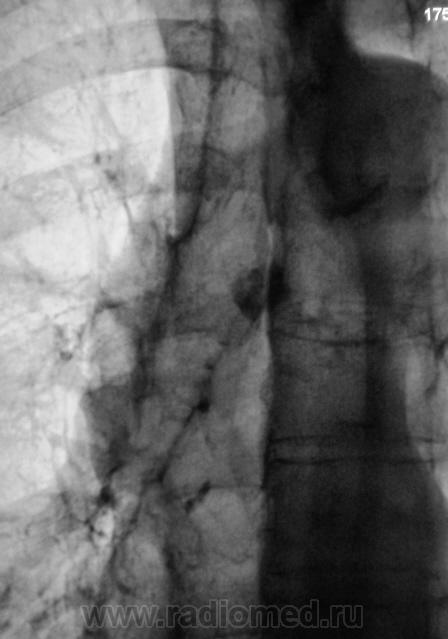

В пр. бифуркации трахеи весьма плотная округлая тень - генез неясен. Сомнительные оч. тени в верхне-латеральной зоне слева. Достаточно хорошо видны гр. позвонки, а в них не вижу корней дужек, да и структура какая-то....  Думаю, Mts-процесс, по-видимому из молочки слева, которая отсутствует.

Согласен с Вами. Мне тоже тень показалась странной, да и укладка не стандартная. Вы правы - состояние после мастэктомии. Решили произвести "боковую".

+ жидкость по междолевке, а в верхнелатеральном отделе слева не осумкование?

"Покрутил" также за экраном, выпота нет. А что с тенью не фоне позвоночника?

Ума не приложу, она и в боковой не отходит от бифуркации. Петрификат? Так как-то не очень.. А Ваш вариант, коллега?

Мы "её" увидели на боковой.

Оттомографировали.

Обызвествленное разрастание хрящевой части ребра?

В грудине участок склероза, видимо все того же происхождения, а по ее передней поверхности та тень, наверное, тоже м.б. метастазом, только в п/к клетчатке. Онкологи часто обнаруживают довольно плотные мета в парастернальной зоне.

Осмотрел пациентку. Над "этим", а "это" значительно выступает - несколько гиперемированная кожа, со множеством телеангионэктазий и и мелкой венозной сеточкой.